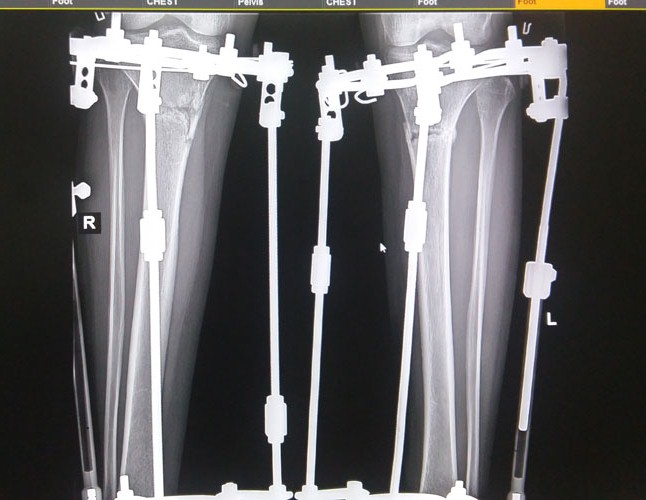

Рентген в 81 день с момента операции.

Дата операции 05.04.2016г.

Дата снятия аппаратов 05.07.2016г.

Срок лечения 90 дней.